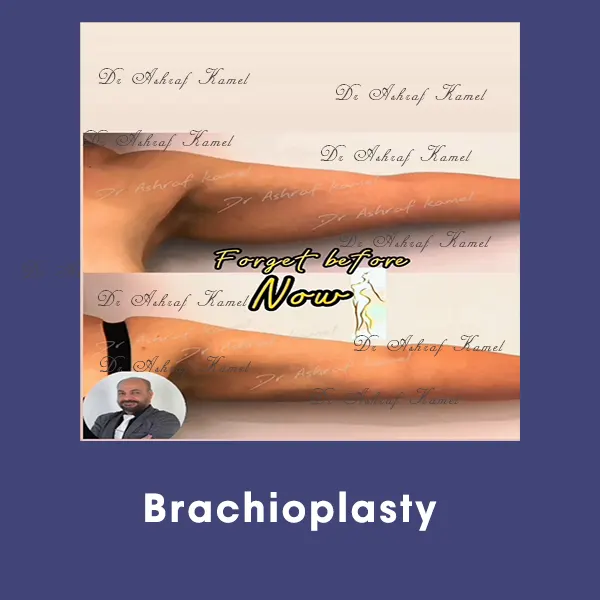

صور حالات مرضى

اشتهر بتقديم احدث تقنيات طب التجميل والجراحات التجميلية وعمليات تنسيق القوام، تكبير وتصغير وشد الثدي وتجميل الأنف وعلاج الترهلات، شد الذراعين و ازالة الترهلات، رفع الأرداف و علاج جراحات السمنة ونحت العضلات والـ6 باكس عالي التحديد، شفط الدهون بالفيزر والجي بلازما واحدث التقنيات بالخريطة الالكترونية، تجميل الجفون، تجميل الاذن وعلاج الاذن الوطواطية.